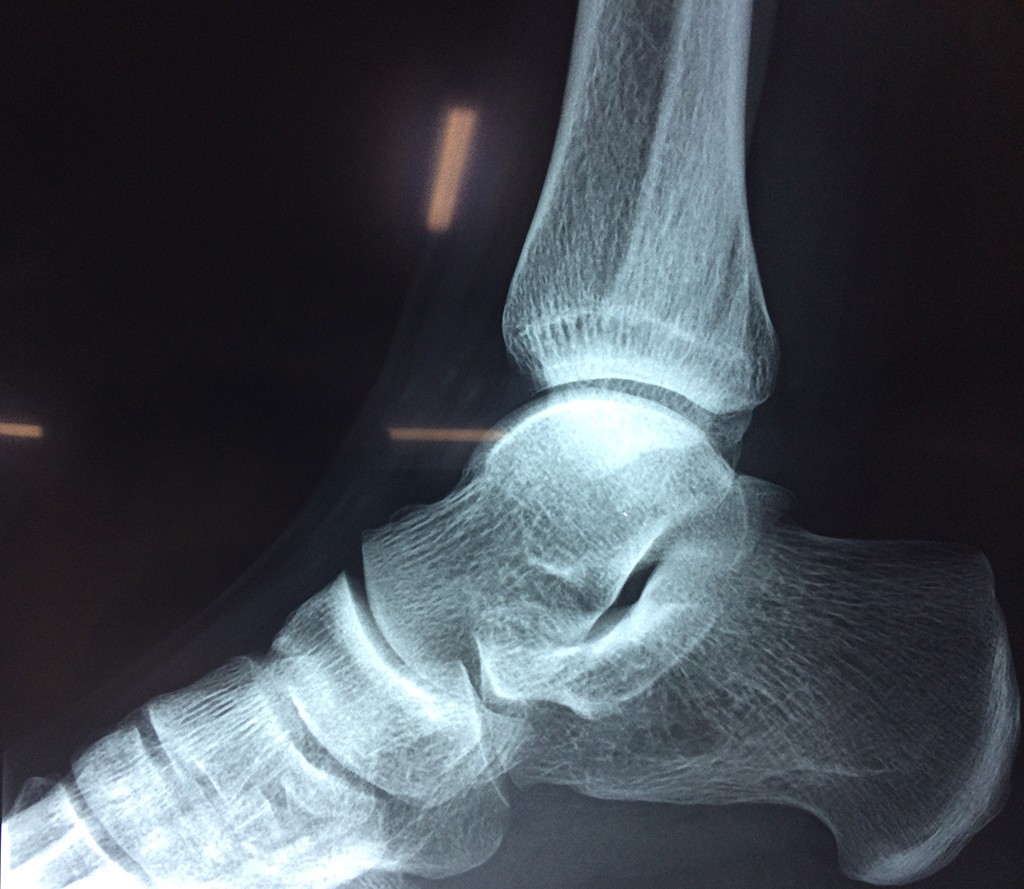

Una fractura de tobillo es la rotura de uno o más de los huesos del tobillo. Estas fracturas pueden ser:

- Parciales (el hueso está sólo parcialmente fisurado, no del todo).

- Completas (el hueso está perforado y está en 2 partes).

- Producirse en uno o ambos lados del tobillo.

Algunas fracturas de tobillo pueden requerir cirugía si:

- Los extremos de los huesos están desalineados entre sí (desplazados).

- La fractura se extiende hasta la articulación del tobillo (fractura intra-articular).

- Los tendones o ligamentos (tejidos que sujetan los músculos y los huesos entre sí) están rotos.

- El médico cree que sus huesos probablemente no sanen apropiadamente sin cirugía.

- El médico considera que la cirugía puede permitirle una recuperación más rápida y confiable.

- En los niños, la fractura involucra la parte del hueso del tobillo donde el hueso está creciendo.

Cuando se necesita cirugía, es probable que esta implique el uso de clavijas de metal, tornillos o placas para sostener los huesos en su lugar mientras la fractura se consolida. Los elementos de soporte pueden ser temporales o permanentes.